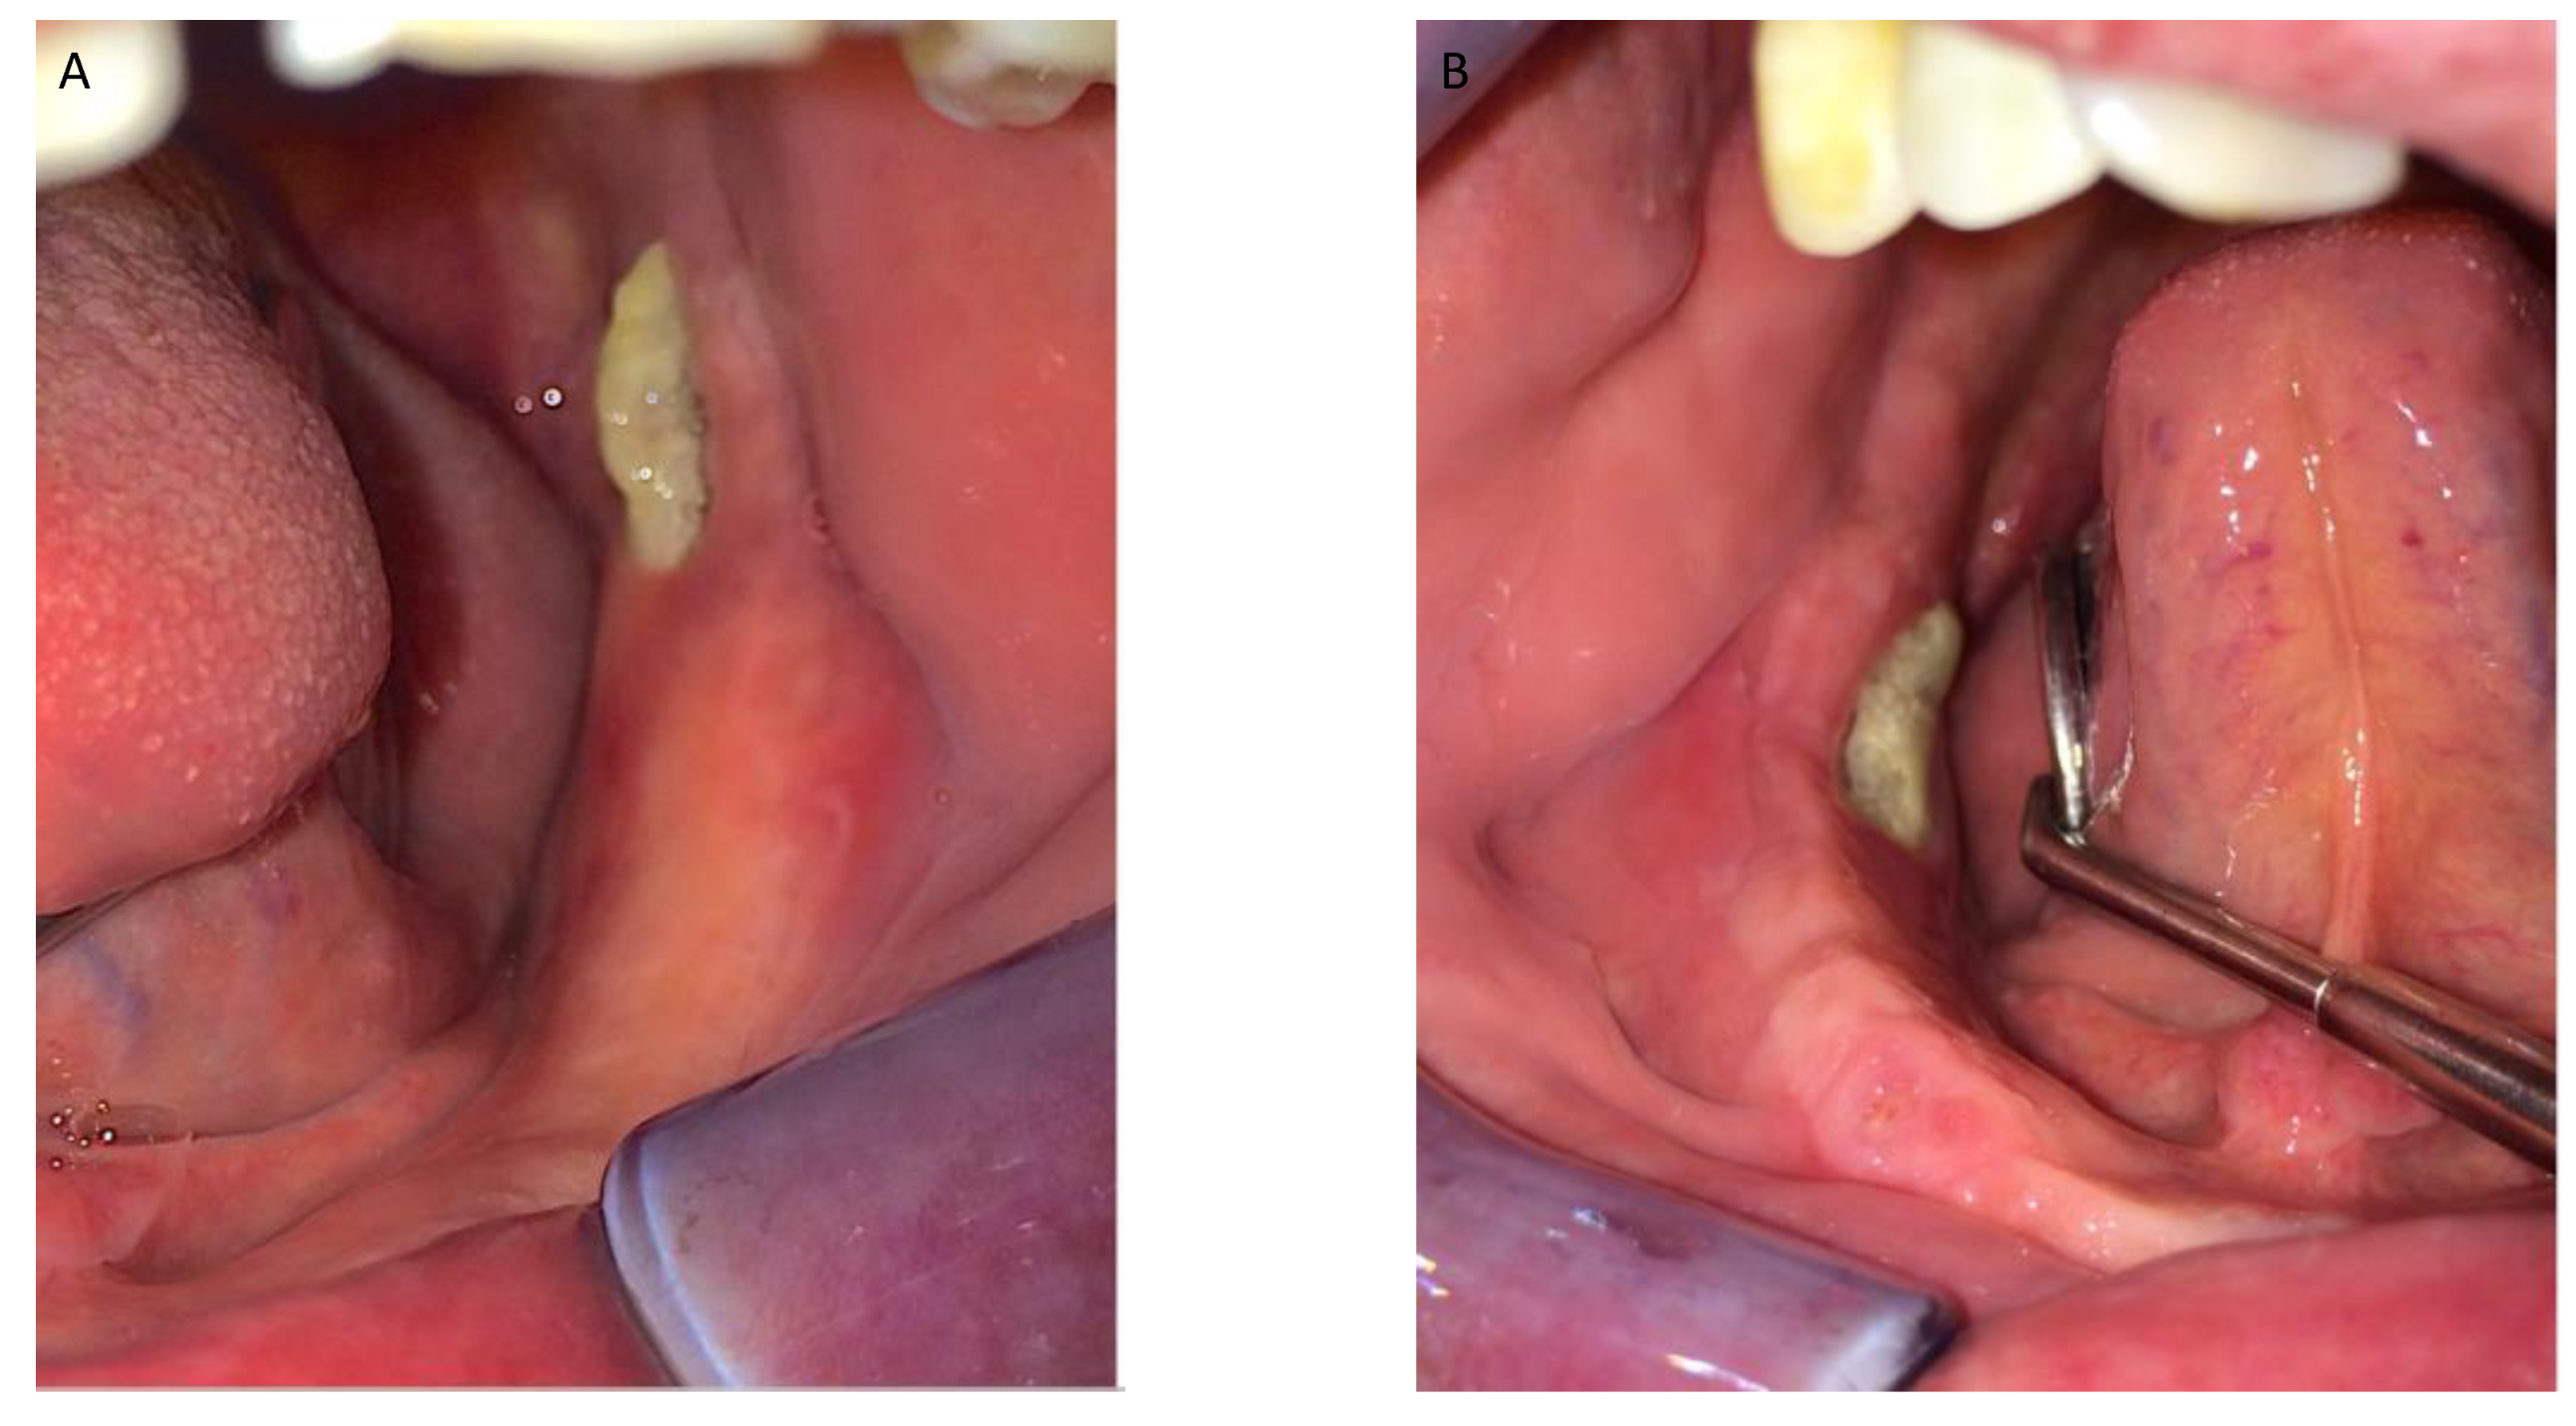

Figure 1, Figure 2, Figure 3, Figure 4, Figure 5, Figure 6 and Figure 7 show the progress of treatment in one of the patients of the test group. In Figure 3 reduction of the medullar space is visible, that may create a chronic ischemic area susceptible to necrosis.

Figure 3.

Pre-operative CBCT of the MRONJ patient, showing a reduction in the medullar space.

Figure 4.

(A–D) Intra-operative view showing operation steps and resected osteonecrotic tissue from the right side of the mandible. After pharmacological preparation with pentoxifylline and tocopherol, the cleavage plane created by the reactive granulation tissue can be clearly seen which tends to separate the necrotic tissue from the healthy bone. Sequestrectomy was made using an osteotome to obtain the necrotic specimen. After the debridement, the bottom of the surgical area was bleeding properly, which creates a favorable environment for healing.